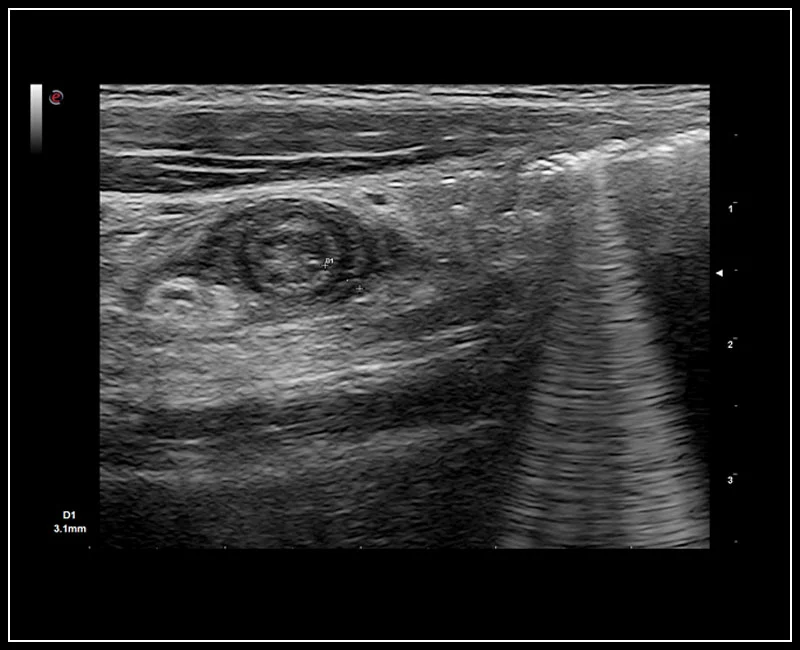

MyLab™9 Platform - Axial view of appendicitis

MyLab™9 Platform - Axial view of appendicitis